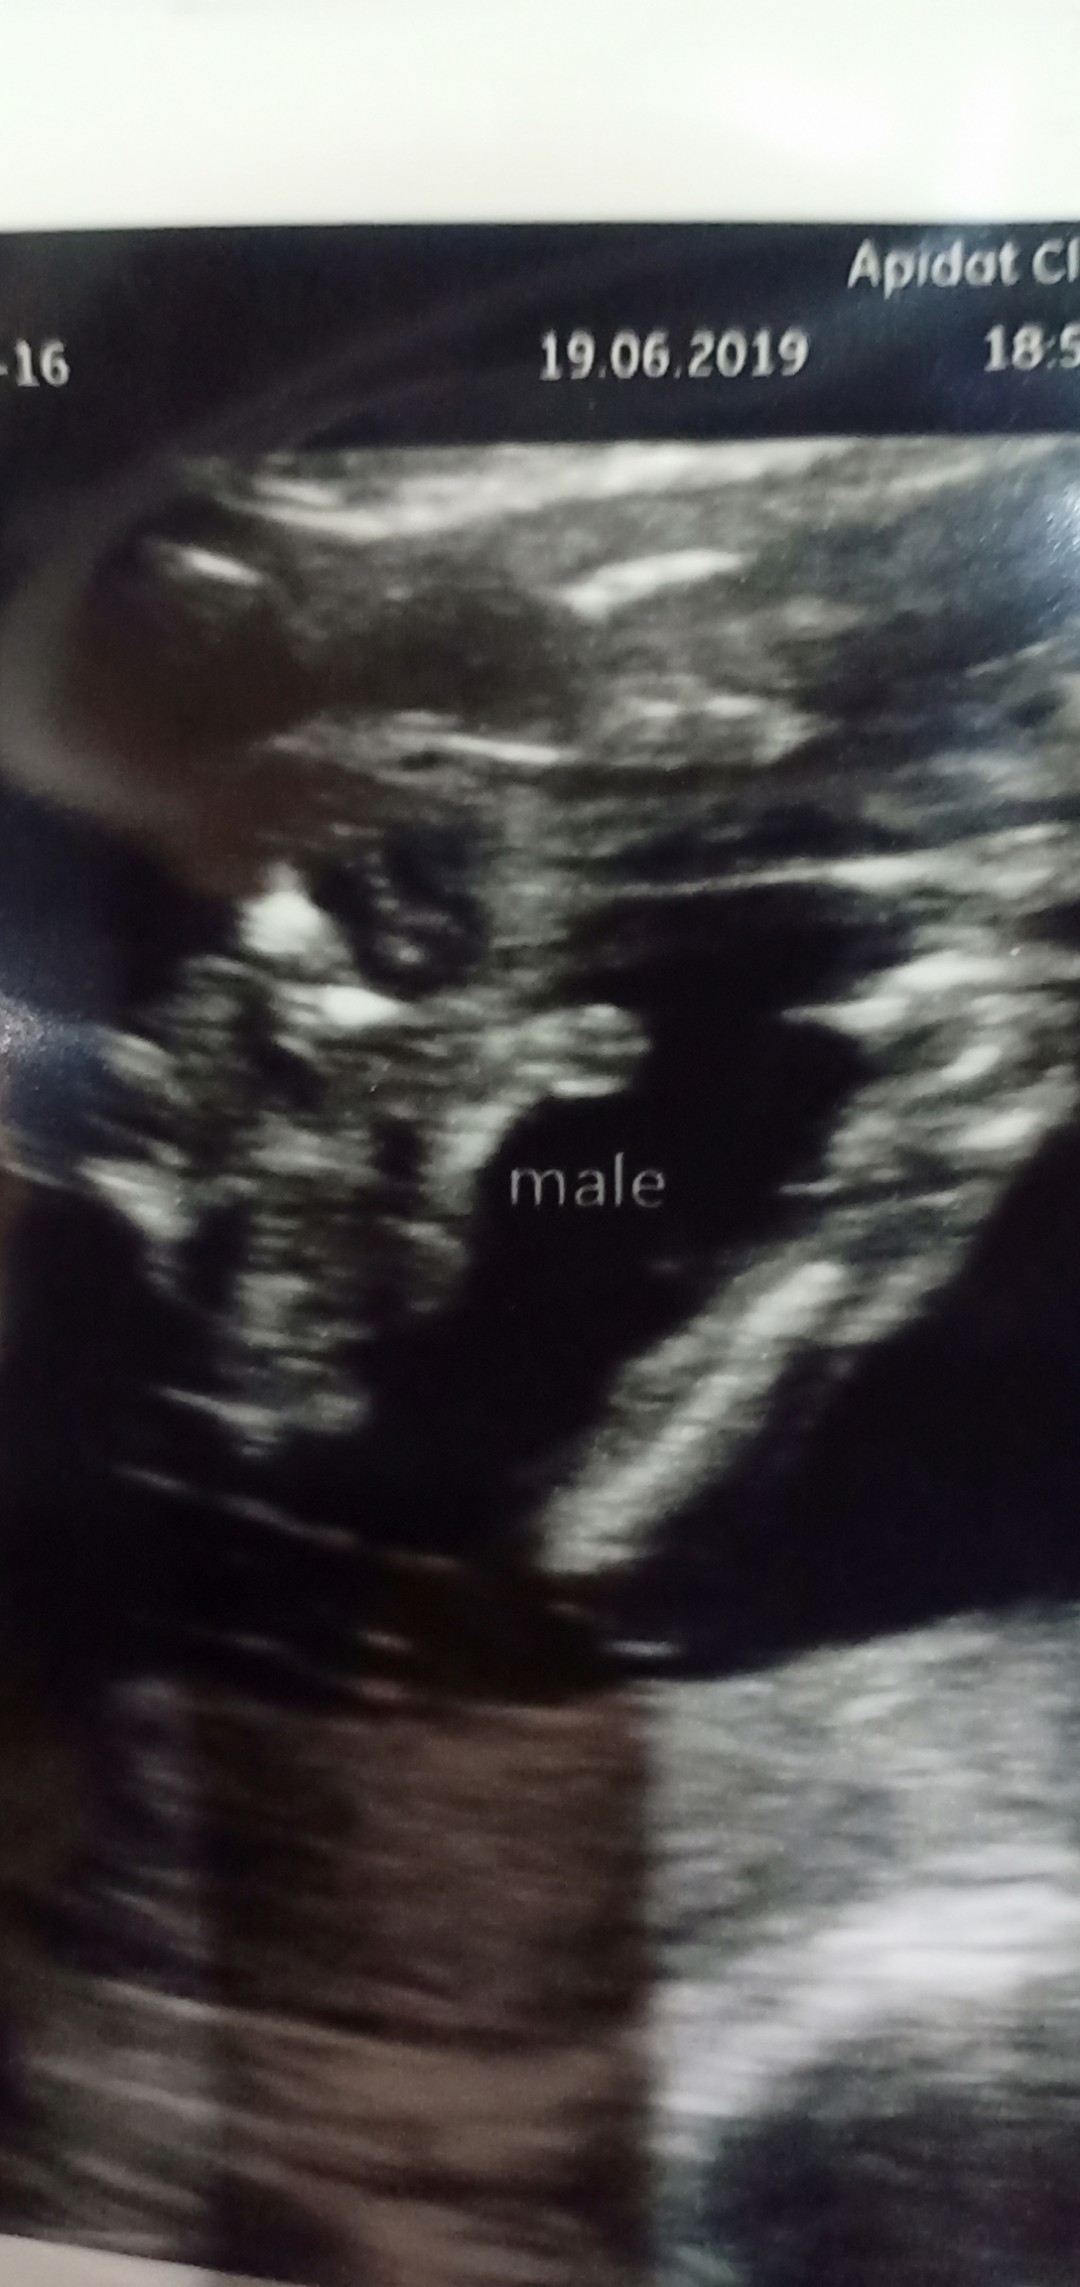

เพศไหนคะเนี้ยยย

ใจอยากได้ลูกชายคร้าาา

ผู้ชายครับ

ผู้ชายค่ะ